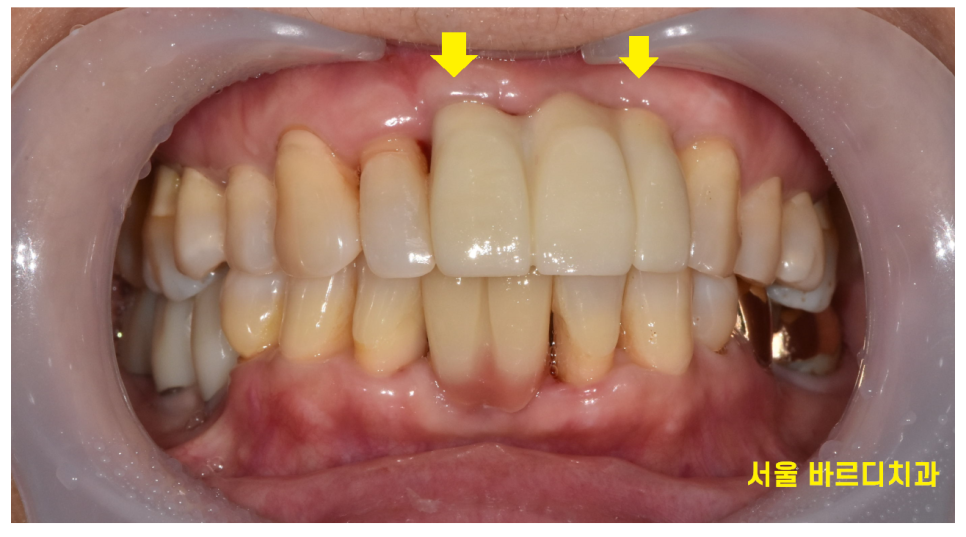

윗니 흔들림으로 방문해주신 환자분입니다.

환자분은 잇몸이 약해서 계속해서 하나씩 치료를 하고 계셨다했는데요.

앞니에 임플란트 한 것도 보이고

보철로 씌운것도 있더라고요~

이 글을 보시는 환자분들은 사진만 봐서는

잘 모르시겠지만

전문가의 보철한 부분이 눈으로는 다 보입니다 ㅎㅎ

완성된 모습입니다.

환자분께서도 가지런하게 재배열된 앞니를 보시면서